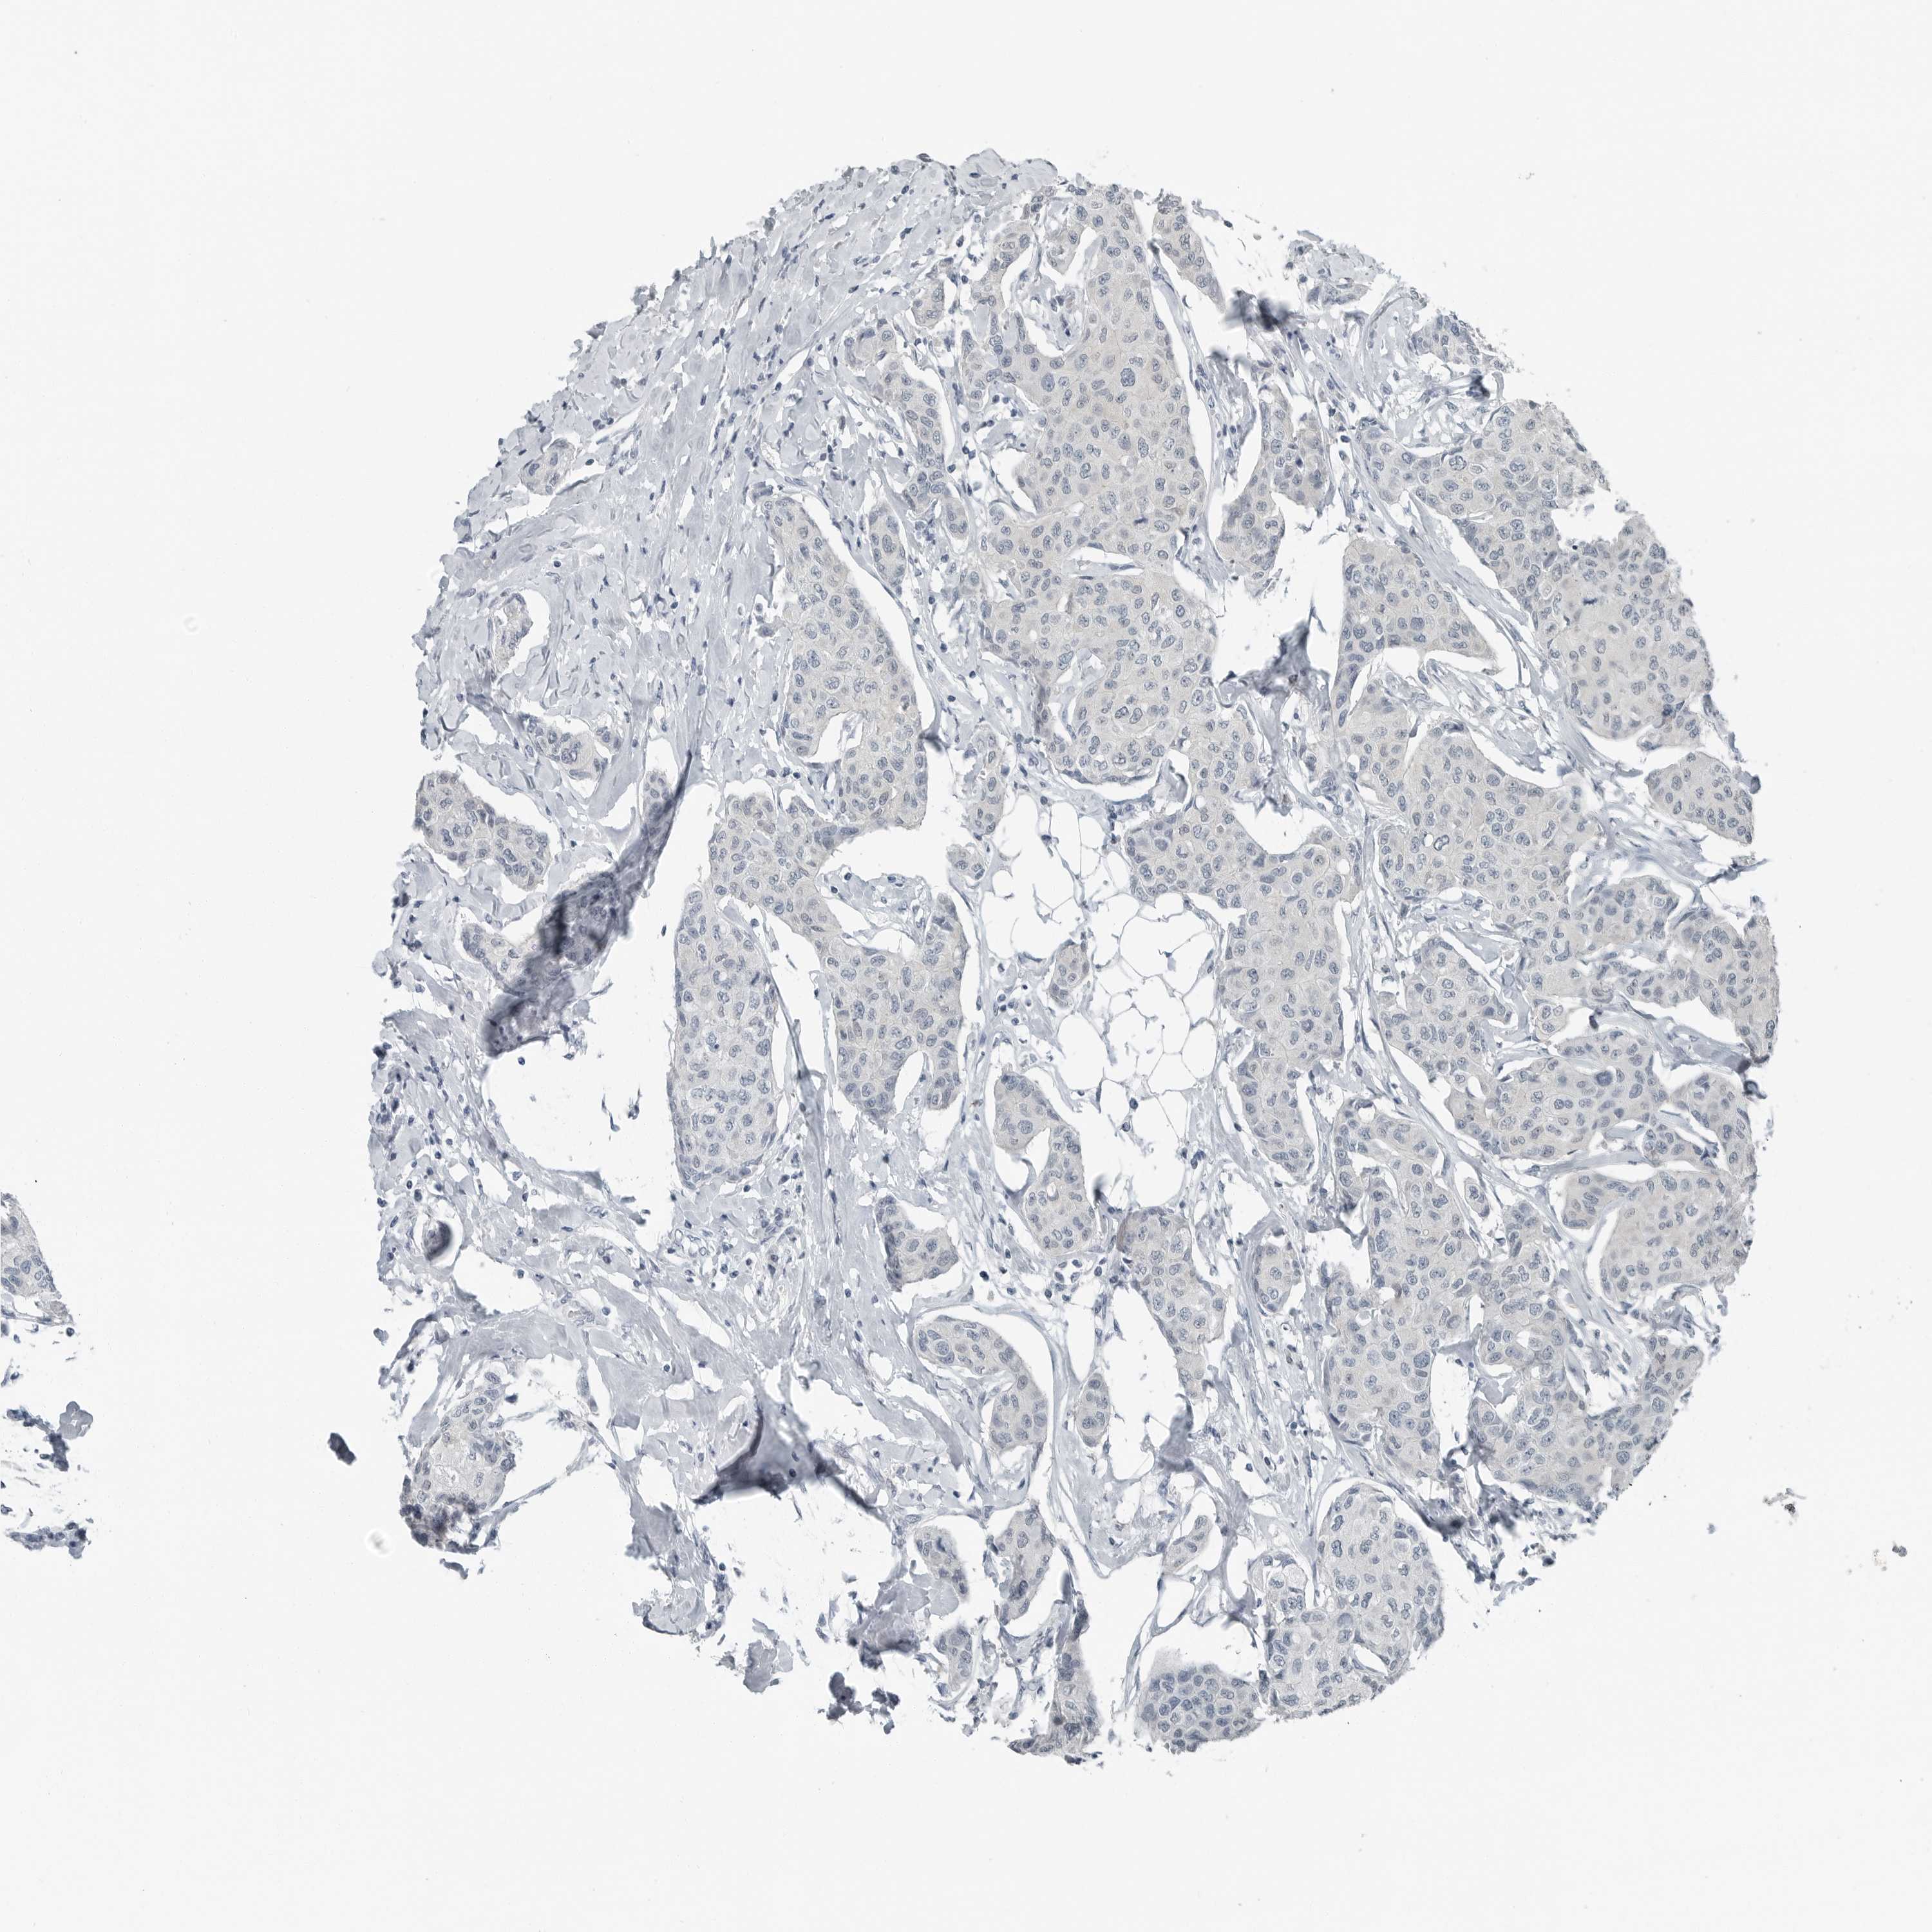

BRCA TCGA BRCA VALIDATION PROTEIN EXPRESSION

ANTIBODIES

AND

VALIDATION